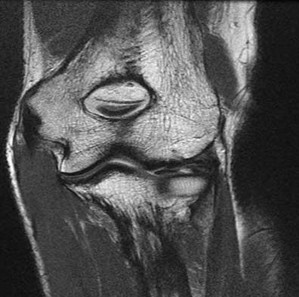

CLINICAL SITUATION FOR QUESTIONS 22 THROUGH 25

A 22-year-old man sustains an injury to his right knee in a motor vehicle collision. Figure 22a is the posterior stress radiograph of the involved knee, and Figure 22b is a selected MR image that identifies the injured structure.

The stress radiographs demonstrate posterior instability of the right knee in flexion. The MR images demonstrate injury to both the anterior and posterior cruciate ligament (PCL), with the stump identified with the arrow on the MR image (Figure 22b). The PCL has 2 functional bands. The anterolateral bundle originates from the roof of the intercondylar notch. It runs in a posterolateral direction onto the tibial crest between the posterior attachment of the medial and lateral menisci. During a double-bundled posterior ligament reconstruction, the

anterolateral bundle is tensioned with the knee in a position of mid flexion. The posteromedial bundle has a variable pattern of tension both in extension and in high flexion. Tensioning of the posteromedial bundle in extension may contribute to resistance against knee hyperextension.

The meniscofemoral ligaments are variably present. Although 93% of knees have been reported to have at least 1 meniscofemoral ligament present, both ligaments are simultaneously present in approximately 50% of knees. The ligament of Humphrey (anterior meniscofemoral ligament) and ligament of Wrisberg (posterior meniscofemoral ligament) are delineated by their anatomic relationship to the posterior cruciate.